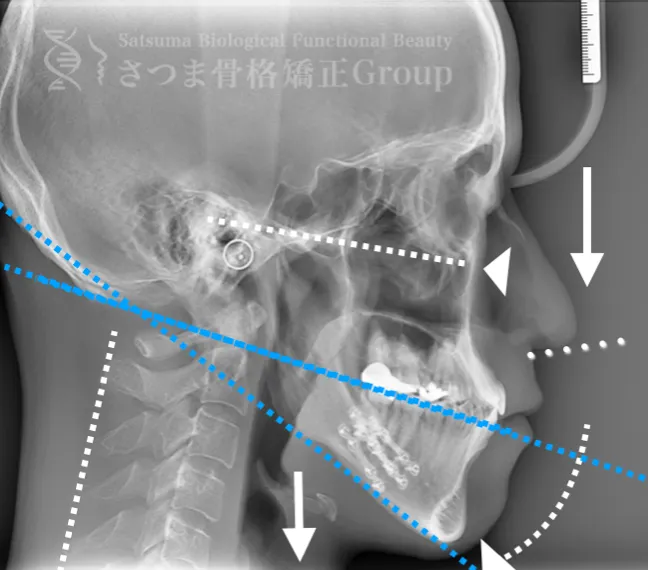

渋谷TMJ歯科クリニックでは、提携先である「さつま骨格矯正」の施術効果を高めるため、レントゲン写真(X-ray images)の撮影を行っています。

顎関節や頭蓋骨、頸椎の位置関係を明確にすることで、施術前の状態を正確に把握できます。

撮影したレントゲン写真は、さつま骨格矯正にて詳細に分析され、施術計画の立案に活用されます。

施術の前後で撮影したレントゲン写真を比較することで、改善の度合いや変化を一目で確認できます。

下顎に強い後方回転あり 中顔面が伸びて下方に落ちる。 中顔面の奥行きを失っている。 下顎の後方回転により上部頚椎C1、C2の可動域が狭い→椎骨動脈への刺激により交感神経が優位。

Mild jaw deformity present. Posterior rotation of the mandible. The midface is elongated and has dropped downward. Loss of depth in the midface. Cervical spine straightening (straight neck).